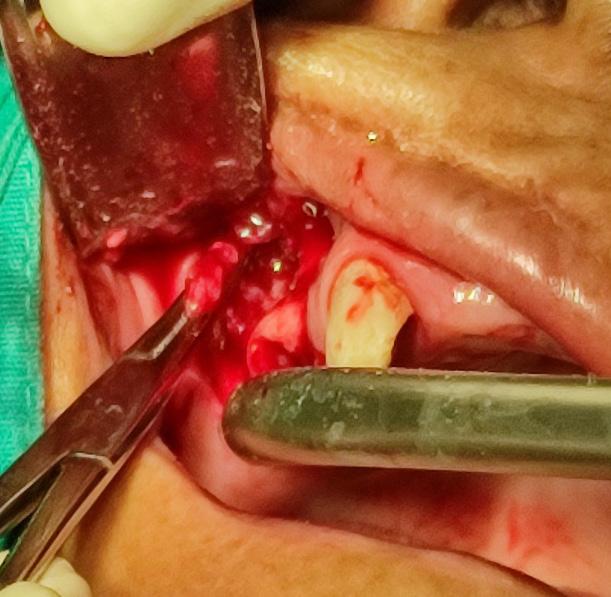

Turn static files into dynamic content formats.

Create a flipbook

Issuu converts static files into: digital portfolios, online yearbooks, online catalogs, digital photo albums and more. Sign up and create your flipbook.